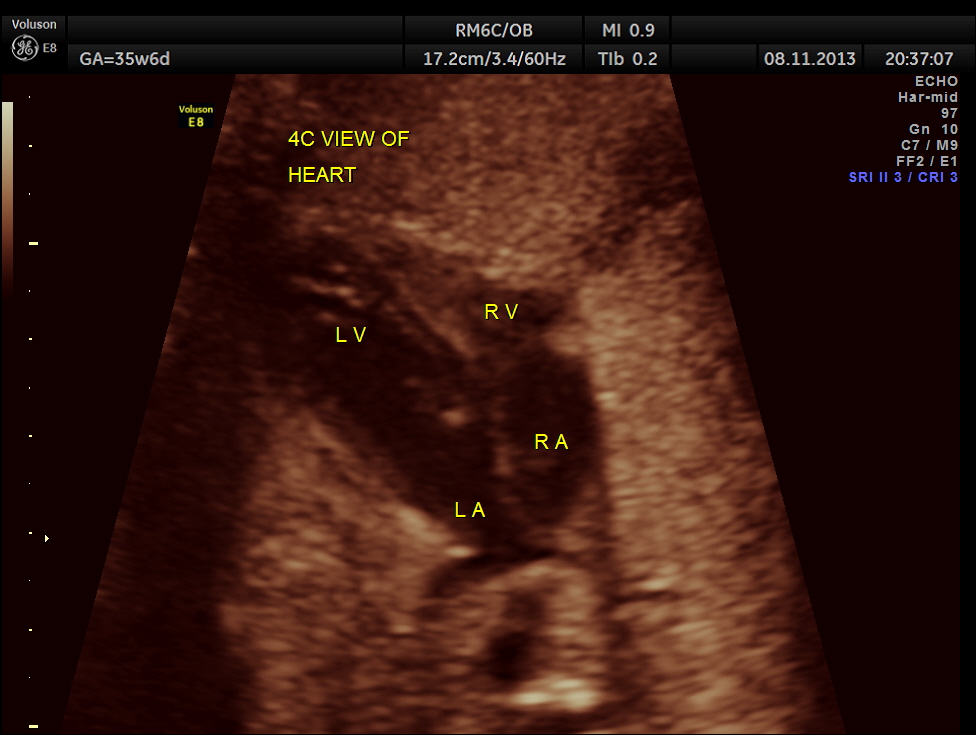

The scan was repeated at 36 weeks of gestation.

BPD, HC show < 2.3 % tile.

AC and FL appear to be normal.

the umbilical artery doppler appears normal.